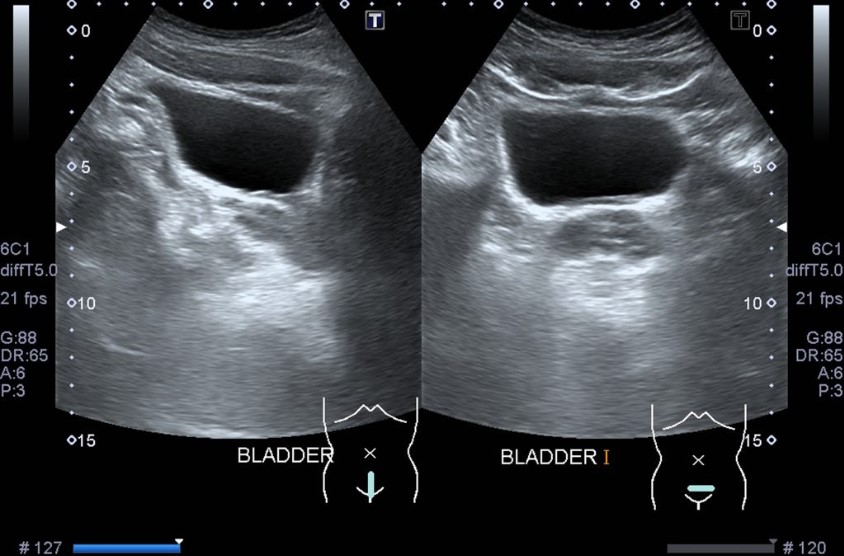

Diverticulum of bladder is a condition where the bladder lining protrudes through a weak or defective part of the bladder wall, forming a pouch or bulge that connects to the bladder lumen.

Bladder diverticula are often asymptomatic, but there can be urinary related symptoms. Some of the symptoms include: Urinary retention (inability to urinate). Urinary tract infection. Blood in the urine. Bladder diverticula are often diagnosed on imaging studies like a CT scan or ultrasound.

Bladder diverticula can be found with an x-ray test of the bladder. The test is done by filling the bladder with a dye that shows up well in x-rays (called a "contrast") and taking pictures. Your health care provider may also look into your bladder with a cystoscope, a long, thin telescope with a light at the end.